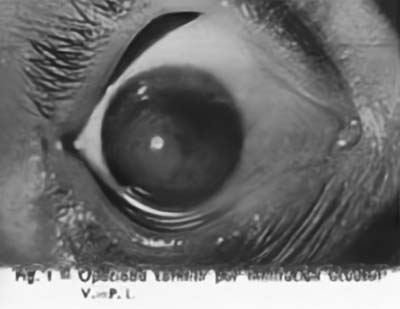

La Cirugía Laminar Refractiva conocida hoy con los nombres de LASIK, PRK, LASEK, se inició a mediados del siglo XX, cuando tratando de solucionar los problemas de visión de los pacientes con Queratocono un oftalmólogo el Dr José I. Barraquer Moner, pudo observar la gran disminución del defecto miópico que padecían, despues realizar sobre los grandes conos un injerto de córnea laminar de 12 mm de diámetro. La aplanación subsecuente de la córnea generaba el cambio refractivo

Inició entonces la observación clínica de los cambios refractivos que ocurrían en las diferentes patologías corneales resultantes de la cicatrices quirúrgicas o accidentales, asi como de las ametropías que generalmente acompañan los valores extremos de la curva corneal ( hipermetropía en los casos de córnea plana, miopía en los casos de córneas muy curvas), confirmando la posibilidad de corregir los defectos de la refracción por modificación del radio de la curvatura corneal.